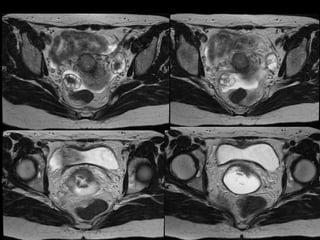

Dr. Hedvig Hricak

HISTORY

•   42 yo female

•   Recent immigrant from China

•   C/O postcoital and intermenstrual bleeding

•   Abnormal GYN exam

•   Abnormal biopsy

•   Further imaging performed

• What is the diagnosis?

• Staging?